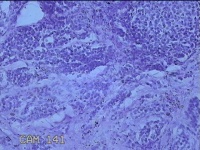

右侧颜面部结节

性别

男

年龄

41岁

临床诊断

皮下结节

一般病史

发现右侧颜面部结节20余年。

标本名称

大体所见

灰白暗红色组织1x0.3x0.2cm一个,表面带梭形皮肤1x0.3cm,皮下见结节0.8x0.3x0.2cm一个,切开挤呈实性,切面灰白粉红色,质中。